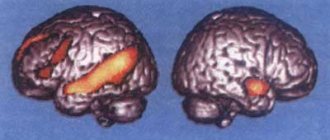

Among 1017 HCP respondents, high temporal variability was found in functional connections formed by the amygdala, orbitofrontal cortex, caudal nuclei, cingulate gyrus, hippocampus, parahippocampal gyrus, lateral and medial geniculate nuclei of the thalamus. The smallest temporal variability was found in the motor and primary visual cortex. The authors explained this by saying that the visual cortex has stronger functional connections between its areas, which allows them to restructure simultaneously. In contrast, areas such as the hippocampus, parahippocampal gyrus, amygdala, and orbitofrontal cortex have functional connections with many other brain regions and change independently of each other. In addition, the visual cortex may have strong functional connections with the motor cortex.

Thus, the authors found little variability over time in the functional connections of the visual cortex. Quite strong changes occurred in the orbitofrontal cortex, amygdala and hippocampus. Consequently, the functional connections of the visual cortex are stronger.

Reduced connectivity of the primary visual cortex with other areas of the brain supports the theory that in patients with long-term schizophrenia, “bottom-up” information processing is impaired, when visual information is transformed by the brain into an image. Perception concentrates more on internal processes, and the person seems to distance himself from what is happening in the environment.

In ADHD, the authors found weak variability in associative connections in the primary visual cortex. This finding supports the hypothesis that in this disorder there is increased sensitivity to visual stimuli, decreased attention during long and laborious tasks, and frequent interruptions due to external stimuli.